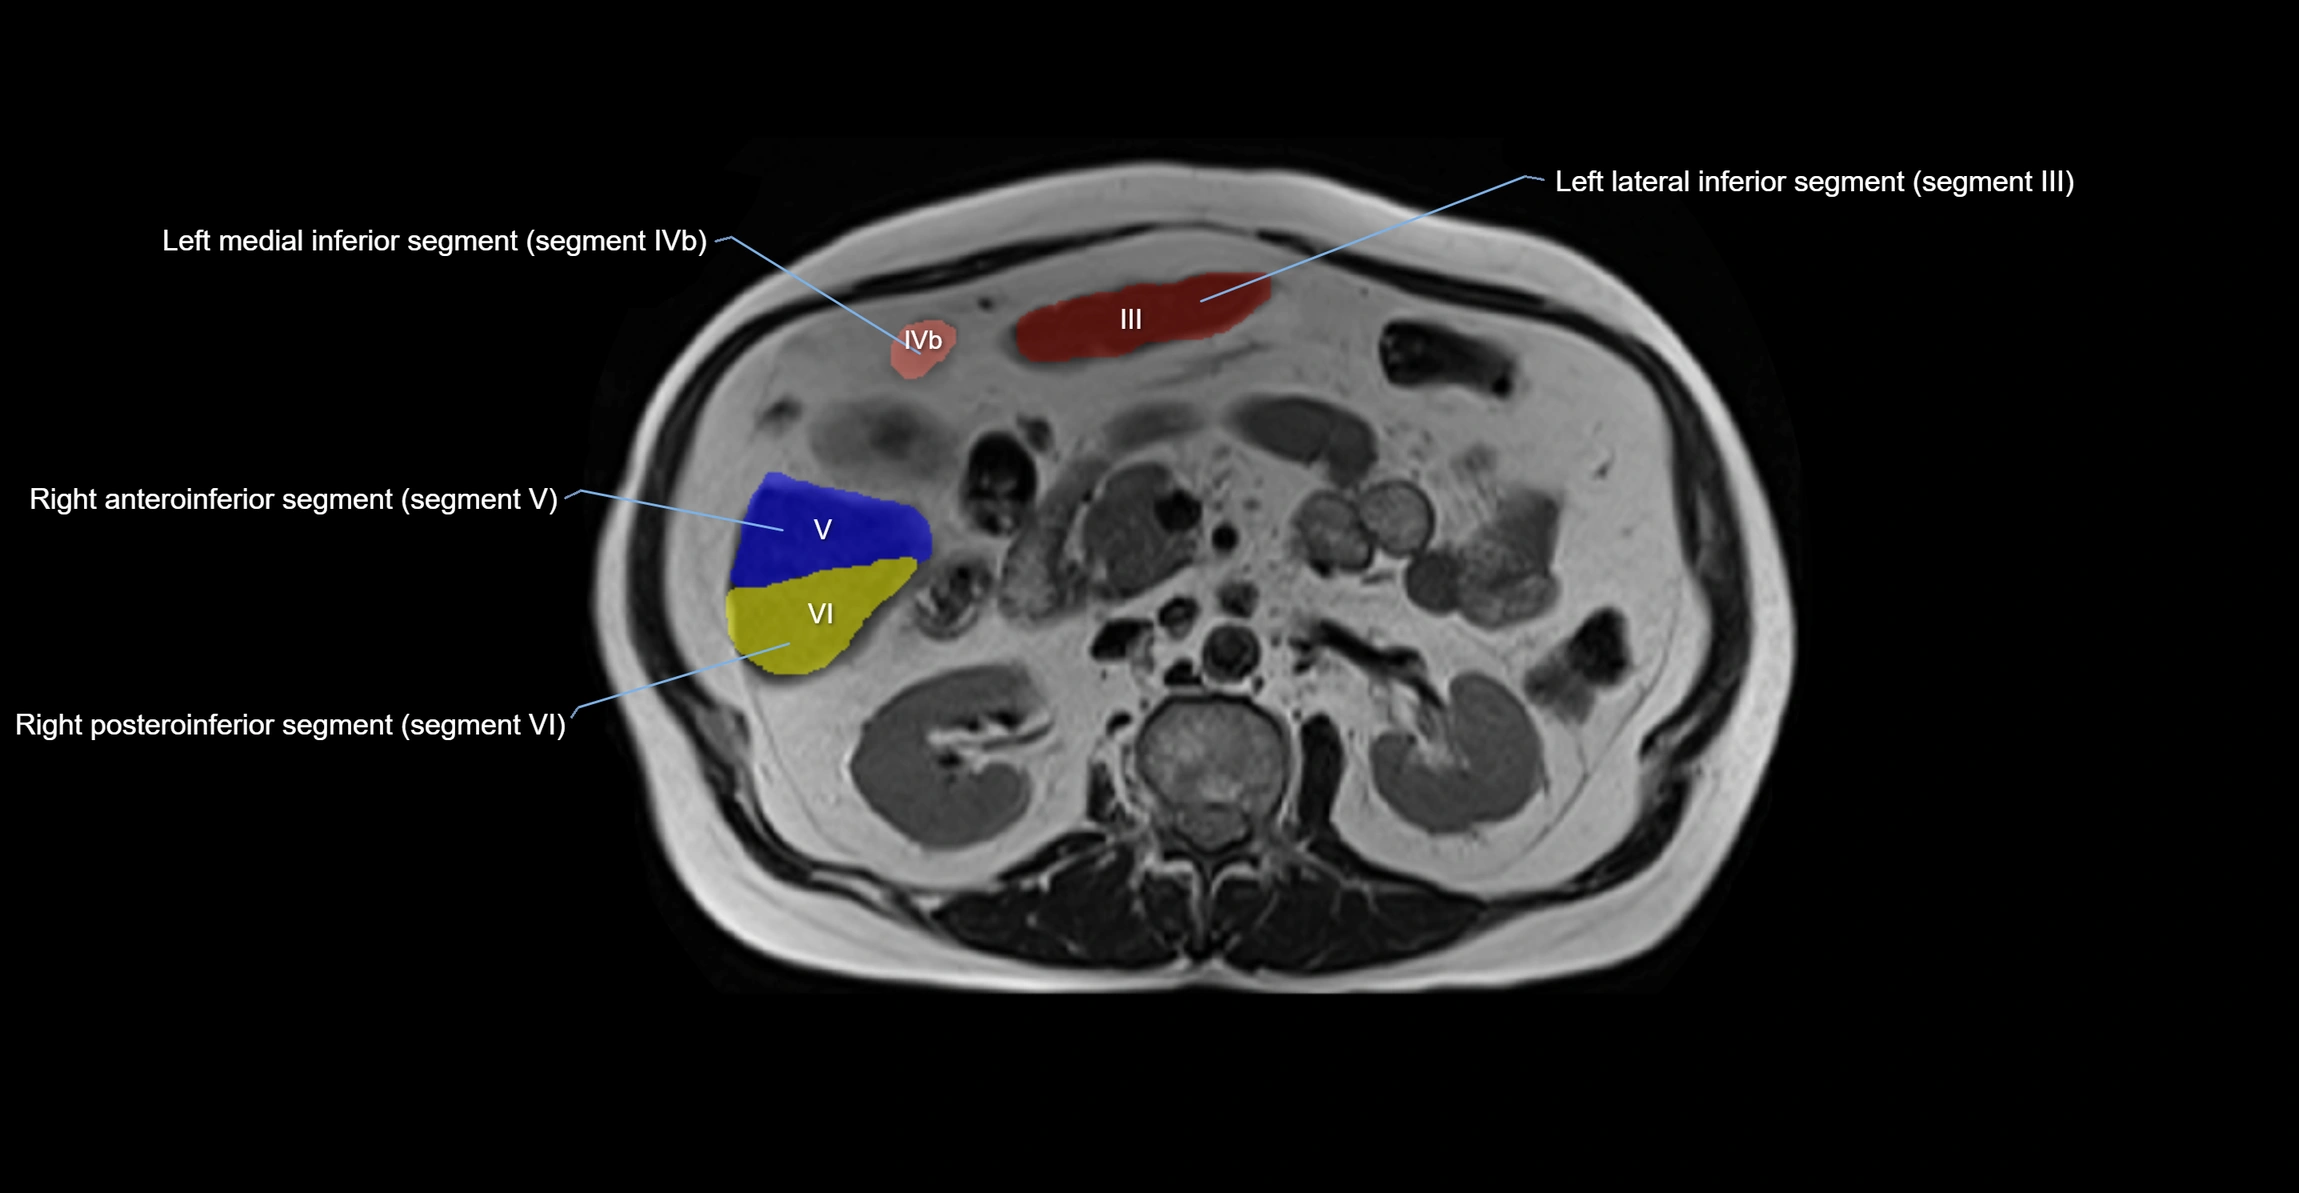

MRI image

image